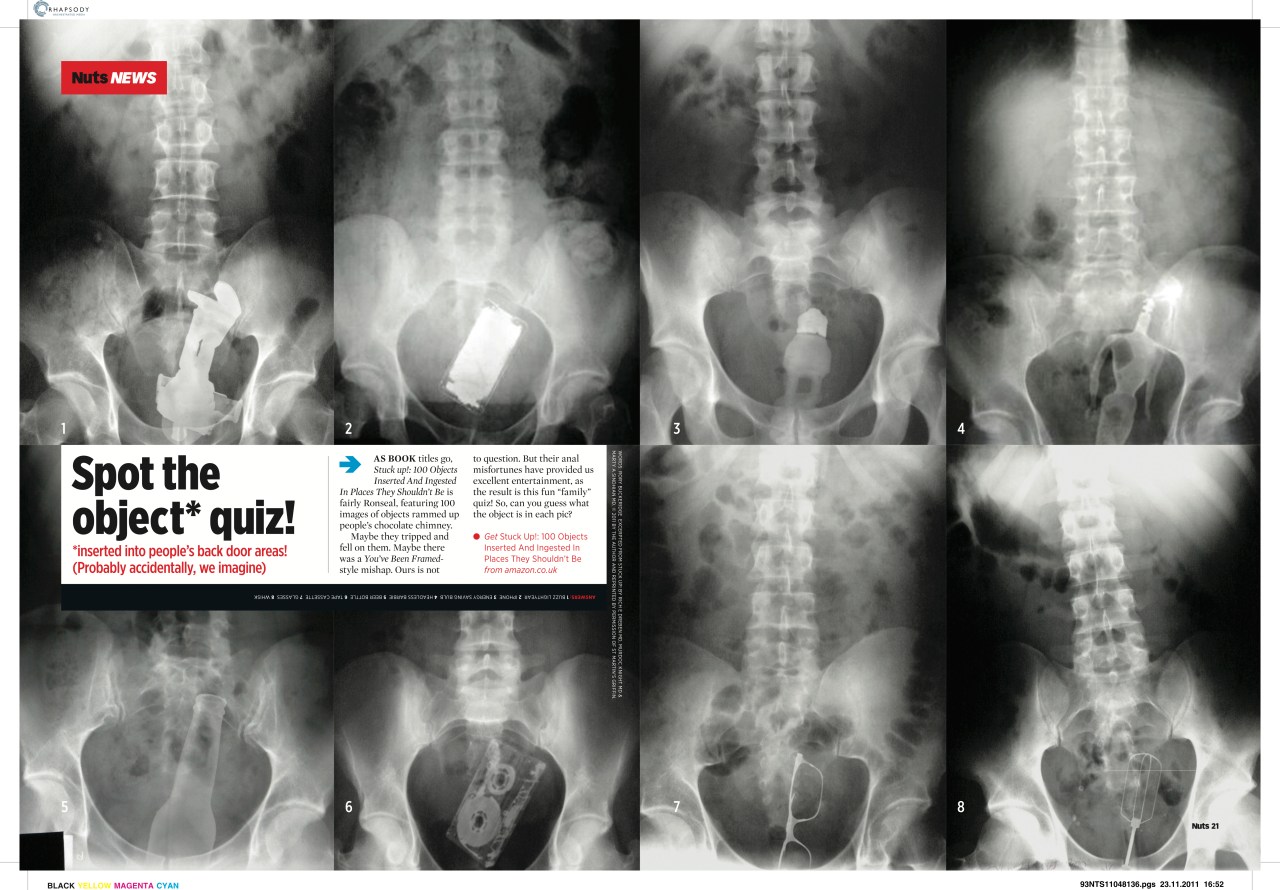

Silly news Date: May 7, 2014Author: rorybuckeridge Post navigation ← Stunts! News stuff → Share this: Share on X (Opens in new window) X Share on Facebook (Opens in new window) Facebook Like Loading... Related